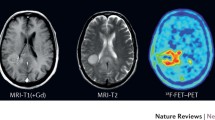

A further study in patients with melanoma brain metastases suggested that amino acid PET using FET can identify checkpoint inhibitor-related pseudoprogression [66•]. In that pilot study comprising 5 patients, imaging findings were correlated with the clinical course after the initiation of the checkpoint inhibitor therapy with ipilimumab. In the case of pseudoprogression, FET PET showed in contrast to the progressive MRI only insignificant tracer uptake, and the patient had a favorable outcome with a progression-free survival longer than 6 months. An illustrative case with treatment-related effects following combined immune checkpoint blockade with ipilimumab and nivolumab identified using FDOPA PET is presented in Fig. 1.

Contrast-enhanced MRI and FDOPA PET of a 56-year-old male patient with a PD-L1-positive and BRAF-mutated malignant melanoma with metastases in the liver, axillary and inguinal lymph nodes, lung, and brain (i.e., in the left cerebellum, left insular cortex, and right precentral and postcentral gyrus). The systemic first-line therapy consisted of encorafenib and binimetinib; the brain metastases were treated concurrently with radiosurgery. After 10 months, new metastases in the lung and left kidney prompted a change in treatment. Radiologically, the brain metastases showed no signs of tumor progression. Two months after initiation of immune checkpoint blockade with ipilimumab and nivolumab, MRI suggested tumor progression of the pretreated metastasis in the left cerebellum (bottom row). In contrast, additional FDOPA PET showed no increased metabolic activity indicating checkpoint inhibitor-related pseudoprogression.